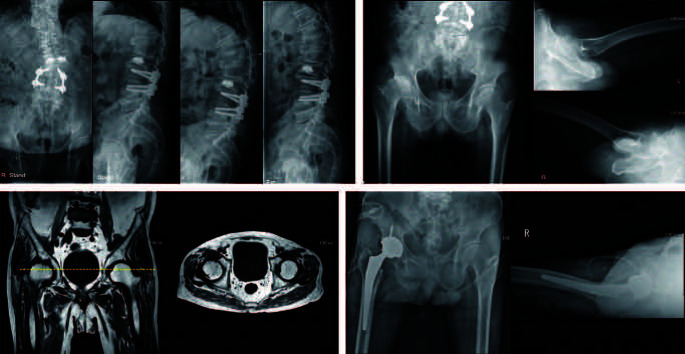

Materials and methods: Patients who underwent total hip arthroplasty (THA) between 2016 and 2022 at a single tertiary hospital were included in the study. Of the 417 patients who underwent primary THA, a retrospective review of 40 patients with previous lesions of the spine was conducted. Patients were stratified to two cohorts: Patients with symptoms related to the spine (Group A), and those with hip-related symptoms (Group B). Pre- and postoperative comparisons of groups A and B were performed.

Results: Improvements in patients' symptoms were observed in groups A and B after THA. In Group A, the mean preoperative visual analog scale (VAS) score was 5.10±0.876, which showed a postoperative decrease to 2.70±1.767. In Group B, the mean preoperative VAS score was 5.10±1.539, which showed a postoperative decrease to 2.67±1.493.

Conclusion: According to the findings, promising results were achieved with THA in treatment of debilitating diseases of the hip for both the prognosis of the disease, as well as the patients' symptoms. In addition, in some cases elderly patients with dual pathologies underwent treatment for spinal lesions without performance of any evaluation related to the hip. Thus, evaluation of a patient's hip must be performed and performance of THA in patients with symptoms even after treatment of spinal lesions is recommended.